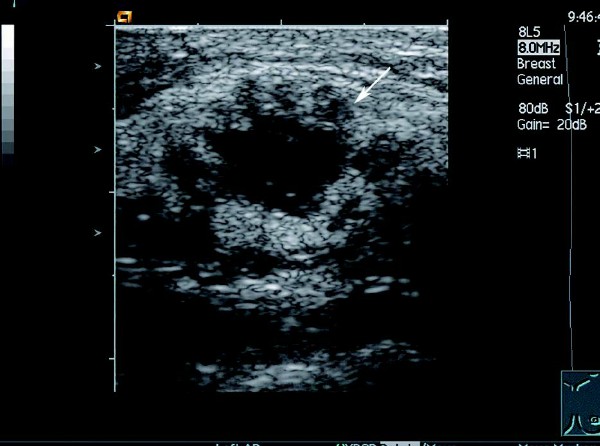

5.CDFI 显示肿块周边及内部血流信号增多,并有新生血管及动-静脉瘘形成,内见穿支动脉血流,形成高速高阻及动静脉混叠现象。

患者,女,46岁。查体时发现右乳腺一肿物,活动度差,质硬。超声检查报告显示:右侧乳腺外上下象限乳腺边缘可见一大小约1.5 cm×1.2cm的偏低回声团,边界不清晰,形态不规则,包膜不明显。内部回声不均匀,可见少量沙砾样强回声点,纵横比>1,偏低回声团后方衰减明显。CDFI:其内可见短管样血流信息,动脉可见高速,高阻血流信息。

超声提示:右侧乳腺实质性肿块伴钙化,考虑乳腺癌